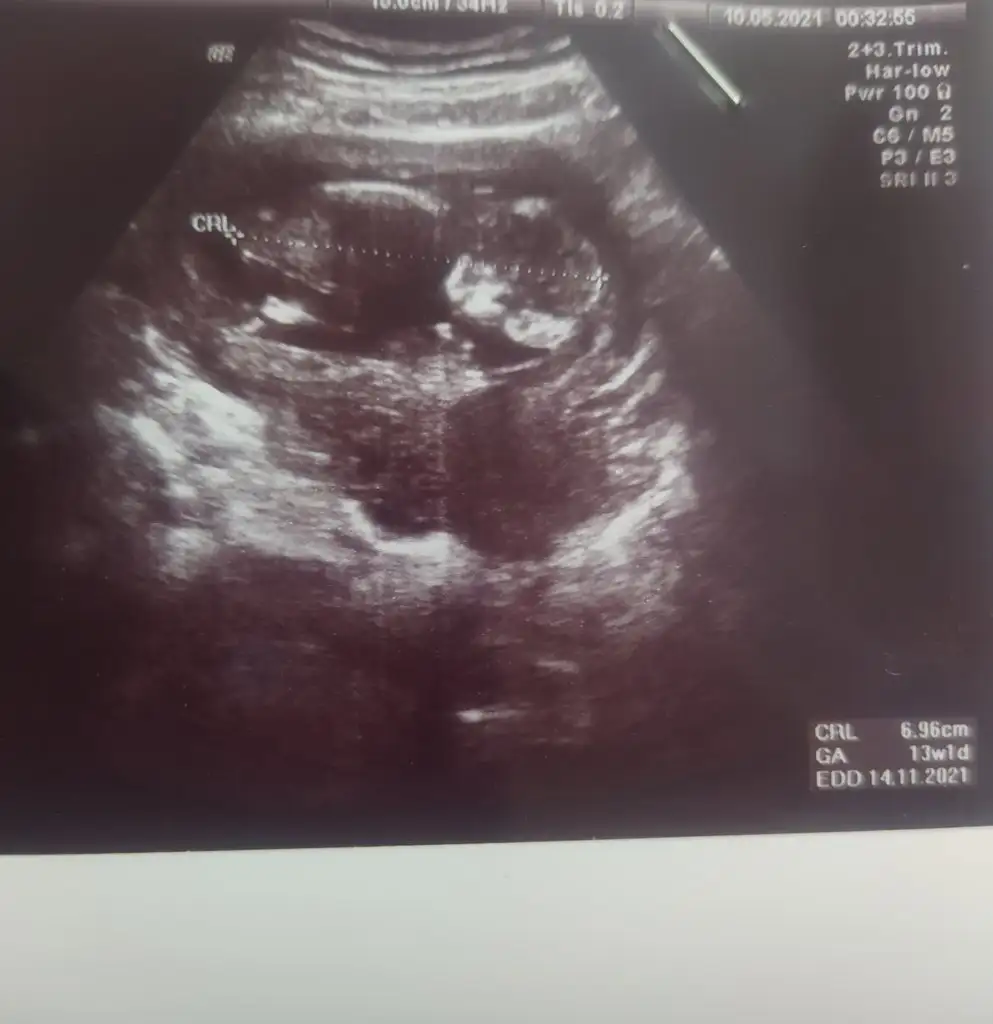

dr soylemeden siz gorun genital nub teorisi ( bebegin cinsiyeti)

Merhaba arkadaslar,aslinda bebegimin cinsiyeti belli,dr.eşime kağıda yazıp verdi ama eşim pazar gunu surpriz yapacagi icin bana søylemiyor,sizin bi tahmininiz varmı?Merakdan çatliyorum.😄😊Eki Görüntüle 2848569

Emin olmadım ama sanki kız gibi geldi bana 🙈 en iyi 11 12 13 haftalar olmalı yada başka USG varsa paylaşın 🤗